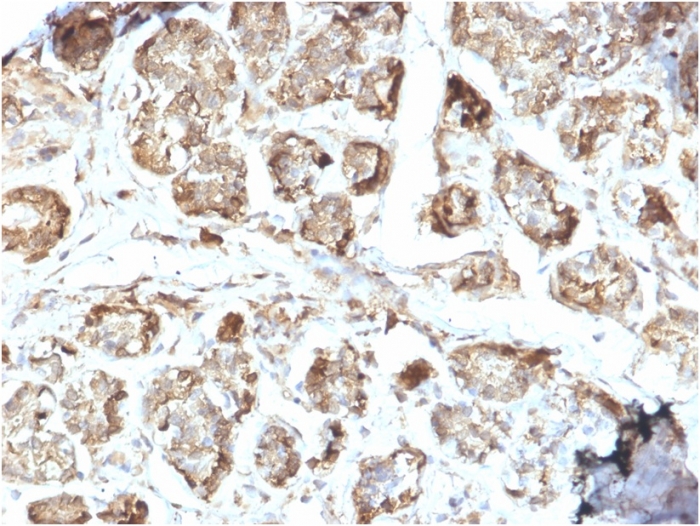

Formalin-fixed, paraffin-embedded human breast carcinoma stained with NME2 / nm23-H2 Mouse Monoclonal Antibody (CPTC-NME2-2).